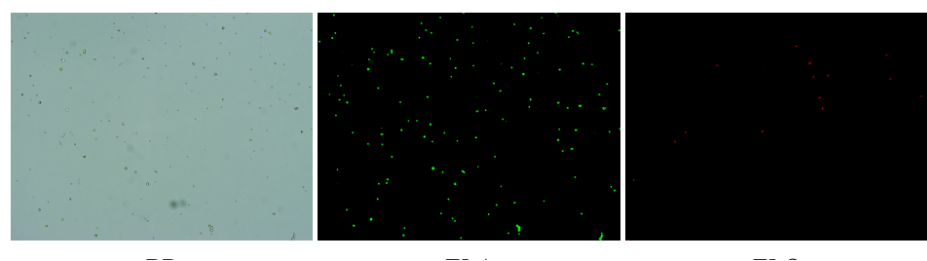

肝臟是人體代謝和解讀的器官,在體內(nèi)發(fā)揮氧化、儲(chǔ)存肝糖、合成分泌性蛋白合成等,肝臟也制造消化系統(tǒng)中之膽汁,人肝約有25億個(gè)肝細(xì)胞。但是解離肝臟組織懸液并不簡(jiǎn)單,首先,肝臟代謝旺盛,離體后肝細(xì)胞無法進(jìn)行正常的有氧糖酵解,細(xì)胞活力會(huì)迅速下降,另外,肝細(xì)胞的線粒體很多,每個(gè)細(xì)胞大約有1000個(gè)左右,遍布于胞質(zhì)內(nèi)。因此,很難得到符合單細(xì)胞測(cè)序要求的單細(xì)胞懸液。百邁客生物在肝臟組織單細(xì)胞懸液制備方面有豐度的實(shí)操經(jīng)驗(yàn),開發(fā)了獨(dú)有的解離體系,下面來看實(shí)驗(yàn)結(jié)果:

實(shí)驗(yàn)結(jié)果

人膽管癌樣本,活性90.45%,結(jié)團(tuán)率7.2%